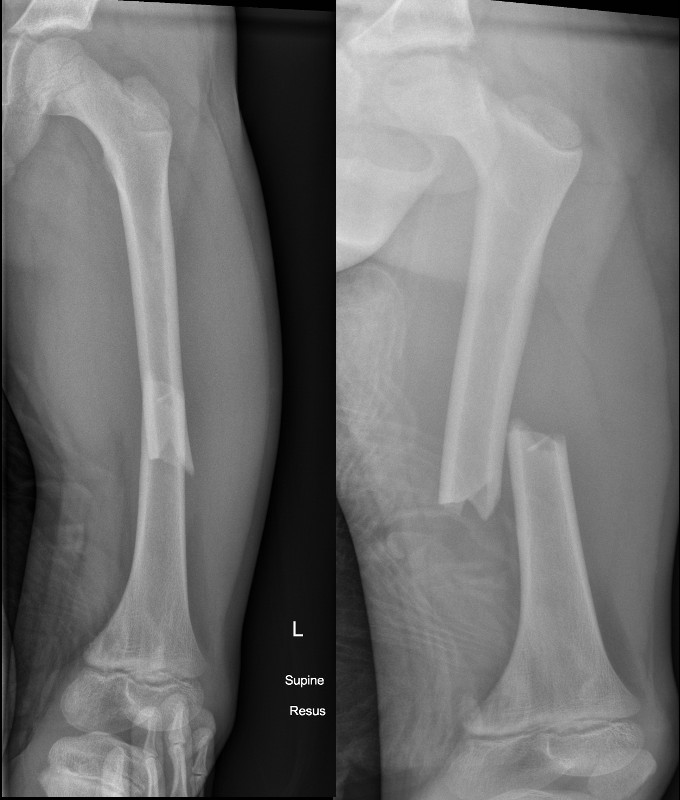

Transverse fracture of femur with displacement and shortening